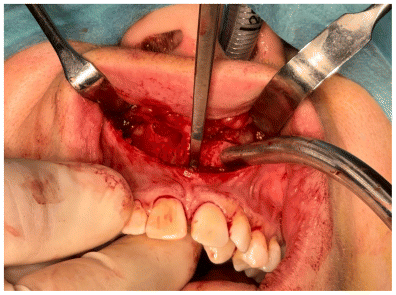

A subperiosteal dissection was performed in the nasomaxillary region, followed by the creation of a myomucosal tunnel in the posterior area of the maxilla to facilitate the passage of the implant. (Figure 5)

The osteotomy was composed of both horizontal and vertical segments (Figures 6,7,8). The horizontal segment was executed at the level of the piriform aperture, extending to the posterior maxilla and zygomatic buttress, with incisions made on the anterior and medial walls of the maxillary sinuses, while maintaining the cut just above the dental roots and following a slightly oblique inclination. This procedure was replicated on both the right and left sides. Subsequently, a vertical osteotomy was performed along the midline between the central incisors, corresponding to the median palatal suture, extending to the terminus of the bony palate at the midline. All osteotomies were carried out utilizing piezoelectric technology, with refinements made using a chisel by flexing (Figure 9).

Subsequent to the osteotomies, controlled activation of the MARPE device was executed to evaluate the resistance of the midline bone. The procedure was concluded with achieving hemostasis, irrigating with sterile saline solution, and suturing. (Figure 10)